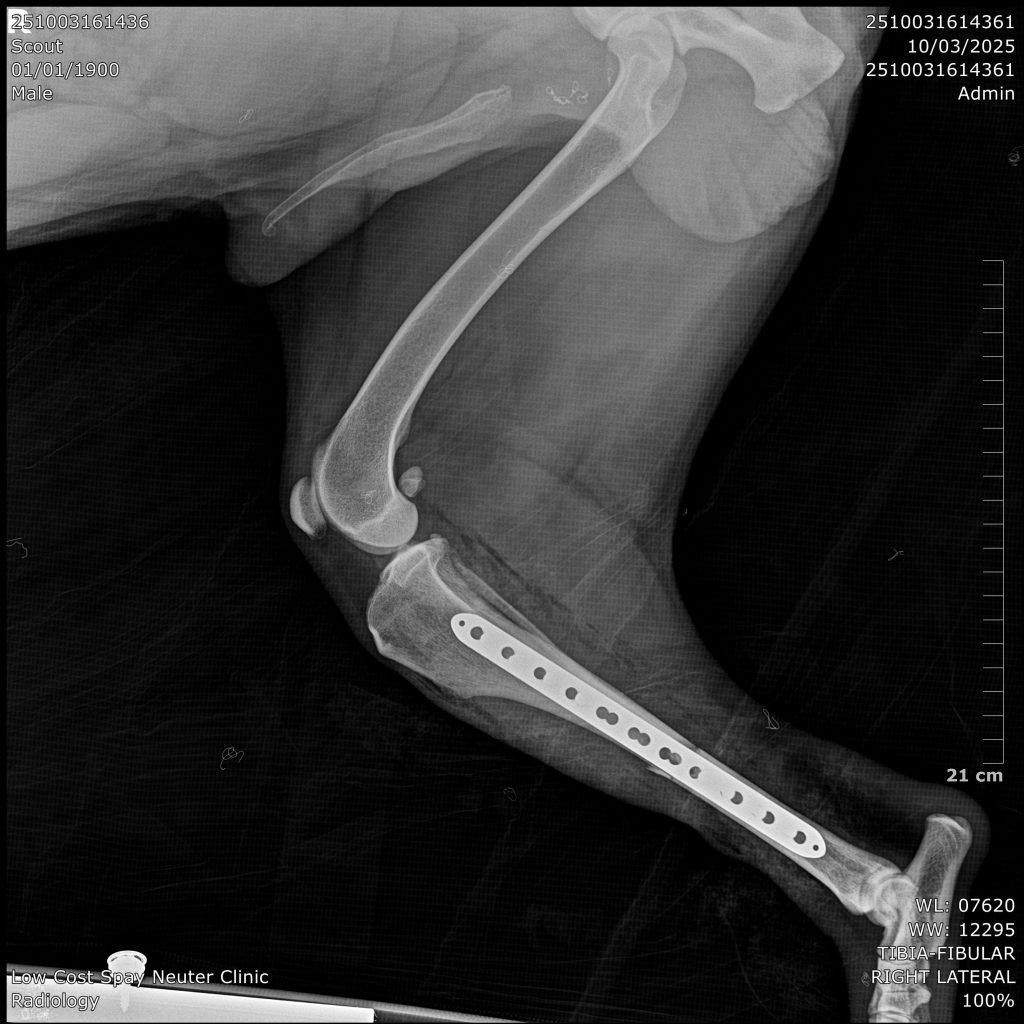

Fracture repair in cats and dogs typically involves surgical stabilization of the broken bone fragments to promote healing. Depending on the fracture type, location, age and body weight various techniques may be used. Proper immobilization, pain management, and rehabilitation are crucial for a successful recovery.

Price starts at $2,000 and will be at the surgeon’s discretion based on findings from x-ray and dependent on surgery time